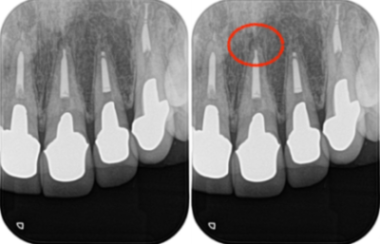

治療詳細レントゲン画像①|【症例】セラミック治療後に発症した根尖性歯周炎に対する歯根端切除術|目白マリア歯科

左:術前 右:術後

治療詳細レントゲン画像②|【症例】セラミック治療後に発症した根尖性歯周炎に対する歯根端切除術|目白マリア歯科

左:術後3ヶ月 右:術後1年

術後およそ2週間で、患者様が訴えていた違和感は大きく改善されました。

その後も3ヶ月、1年と経過を追って確認した結果、現在に至るまで外科手術による瘢痕はほとんど見られず

美しい歯のラインを維持したまま、無事に治療を完了することができました。